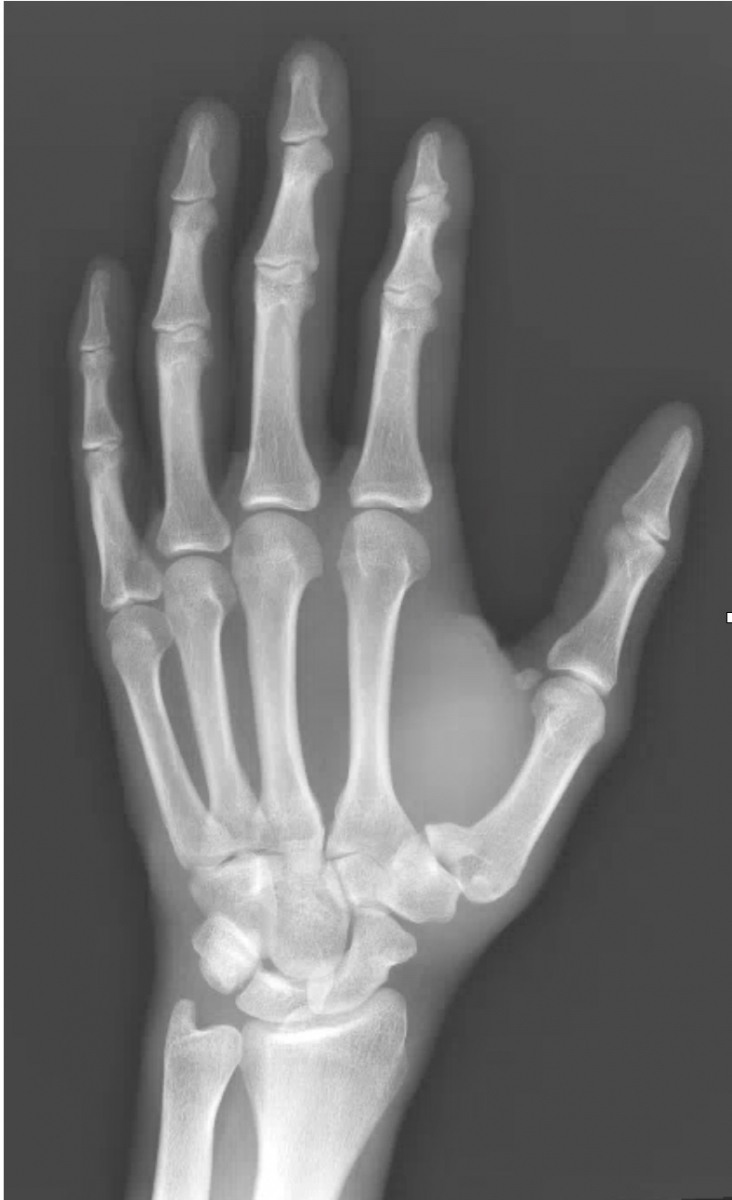

What’s the diagnosis? Gepost op 28 juni 201828 juni 2018 door netwerkvsseh What’s the diagnosis? @emdaily.cooperhealth.org Dit delen: Delen op X (Opent in een nieuw venster) X Share op Facebook (Opent in een nieuw venster) Facebook Delen op LinkedIn (Opent in een nieuw venster) LinkedIn E-mail een link naar een vriend (Opent in een nieuw venster) E-mail Afdrukken (Opent in een nieuw venster) Print Vind-ik-leuk Aan het laden... Gerelateerd